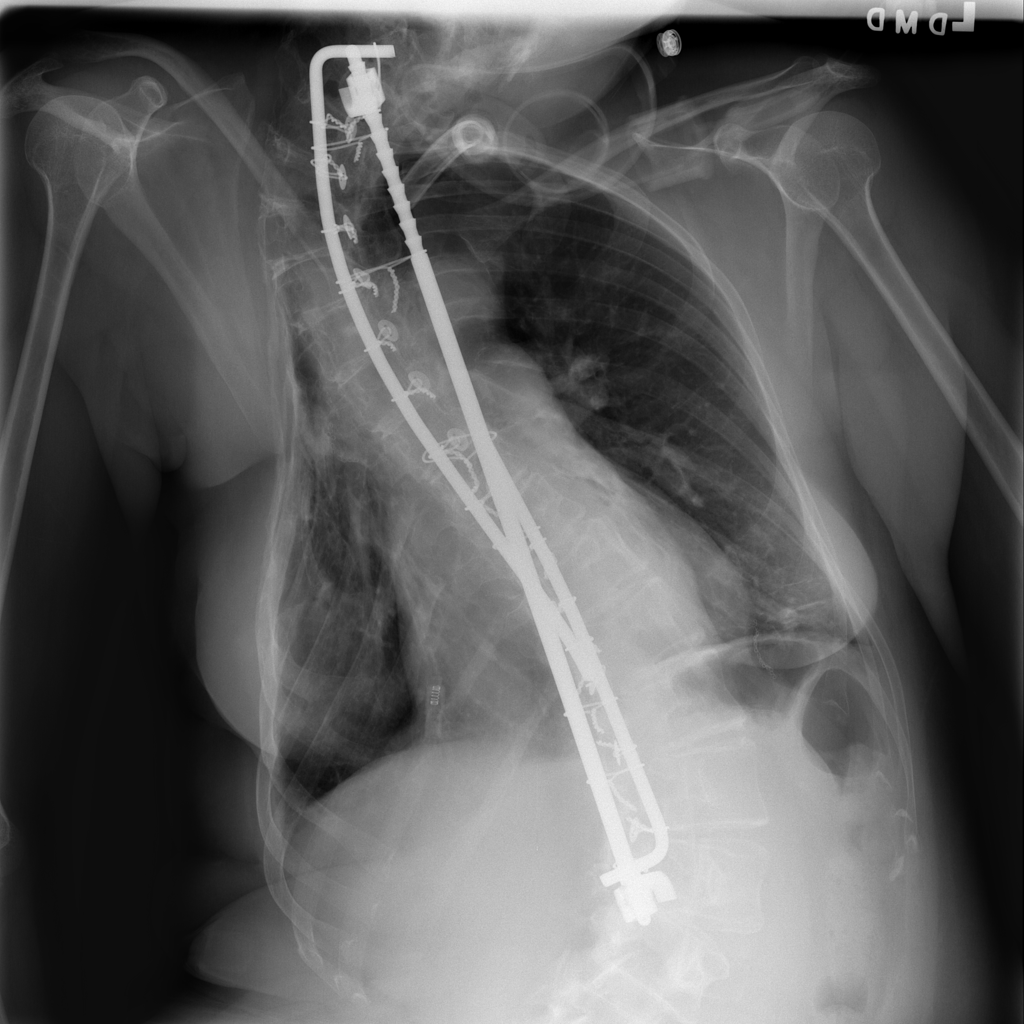

PAT-BC92 · IMG-003Atelectasis

PAT-BC92 · IMG-003

AP

PAT-F97C · IMG-000Atelectasis

PAT-F97C · IMG-000